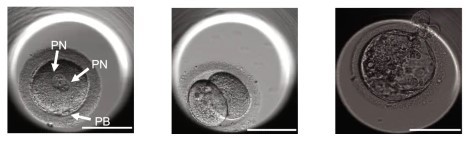

電気刺激とロスコビチン処理により活性化されたSCNT卵子の受精後の発生過程

精子と受精させた実験では、一部の胚で体細胞由来と精子由来の染色体が統合された。しかし、染色体数の不均衡により多くが異数体となり、初期段階で発育が停止。胚盤胞(受精から約5〜6日後に形成される状態)まで発育したのは8.8%にすぎなかった。